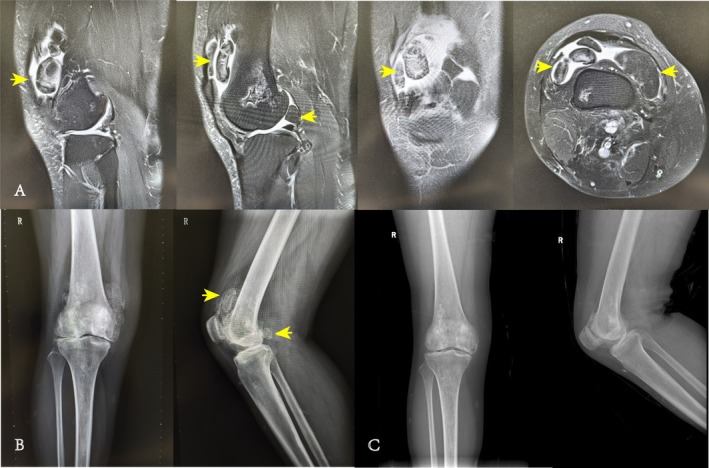

目的:滑膜软骨瘤病是一种非常罕见的良性疾病,主要发生在膝关节,可导致疼痛,活动受限,并可能对关节和软骨造成不可逆的损伤。尽管关节镜技术在滑膜软骨瘤病的手术治疗中得到了应用,但对其疗效的长期评估仍然缺乏。本研究的主要目的包括:(i)调查膝关节滑膜软骨瘤病患者关节镜手术的长期疗效;(ii)确定影响患者术后功能改善的因素。方法:我们对2009年6月至2020年1月在我院接受关节镜滑膜切除术和松体切除术的所有膝关节滑膜软骨瘤病患者进行了回顾性分析。所有病例随访时间均超过5年。资料收集包括人口学资料、临床疗效指标(VAS、oos、WOMAC等)、影像学表现、患者对手术结果的主观满意度。数据分析选择基于正态性检验结果的t检验、方差分析、非参数检验和相关方法。结果:共入组13例患者,男4例,女9例,平均随访时间113.15±30.45个月(61 ~ 145个月)。所有患者均无术后并发症、复发、恶性转化,且所有患者在随访3个月、6个月、1年、5年及末次随访时VAS评分、oos评分、WOMAC评分、Lysholm评分均有显著改善(p)。结论:本回顾性研究表明关节镜下治疗膝关节滑膜软骨瘤病是有效、安全的。它可导致干预后症状和功能的立即改善,并具有持续的长期益处。

Objective: The synovial chondromatosis is an exceptionally rare benign condition, predominantly found in the knee joint, and can result in pain, restricted mobility, and potential irreversible damage to the joint and cartilage. Despite the utilization of arthroscopic techniques in the surgical management of synovial chondromatosis, there remains a paucity of long-term assessment regarding its efficacy. The main objectives of this study include: (i) investigating the long-term efficacy of arthroscopic surgery in patients with knee synovial chondromatosis;(ii) identifying factors influencing functional improvement in patients post-surgery function.

Methods: We conducted a retrospective analysis of all patients with synovial chondromatosis of the knee who underwent arthroscopic synovectomy and loose body removal at our institution between June 2009 and January 2020. The follow-up period for all cases exceeded 5 years. Data collection included demographic details, clinical efficacy indicators(VAS, KOOS, WOMAC, etc.), imaging findings, and subjective satisfaction of patients with surgical outcomes. Data analysis selected t-tests, ANOVA, non-parametric tests, and correlation methods based on normality test results.

Results: We enrolled a total of 13 patients, including 4 men and 9 women, with a mean follow-up of 113.15 ± 30.45 months (range 61-145). There were no postoperative complications, recurrence, or malignant transformation in all patients, and the VAS scores, KOOS scores, WOMAC scores, and Lysholm scores of all patients were significantly improved at 3 months, 6 months, 1 year, 5 years, and the last follow-up (p < 0.05). However, one patient experienced osteoarthritis progression, necessitating arthroplasty.

Conclusion: This retrospective study demonstrated that arthroscopic treatment for knee synovial chondromatosis is effective and safe. It leads to immediate post-intervention improvement in symptoms and function, with sustained long-term benefits.